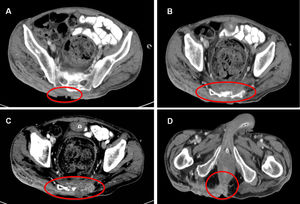

Abdominal CT scan showed extensive involvement of the subcutaneous tissue from approximately L4 to the coccyx, with erosion of the sacrum and destruction of the coccyx. In one area, the external anal sphincter was also involved on the posterior side (Fig. 2A–D).